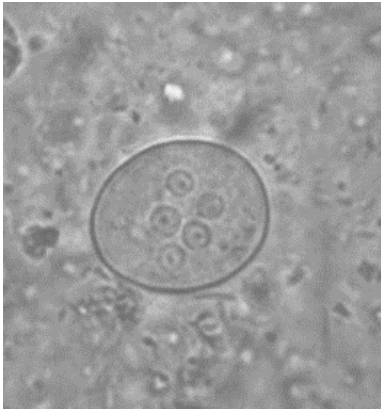

Observe a imagem a seguir.

Disponível em: <http://www.icb.usp.br/~livropar/img/capitulo6/8.html>. Acesso em: 29 set. 2024.

Essa imagem foi obtida em um microscópio óptico no aumento de 400x a partir de um sedimento fecal. Na imagem, observa-se um cisto de